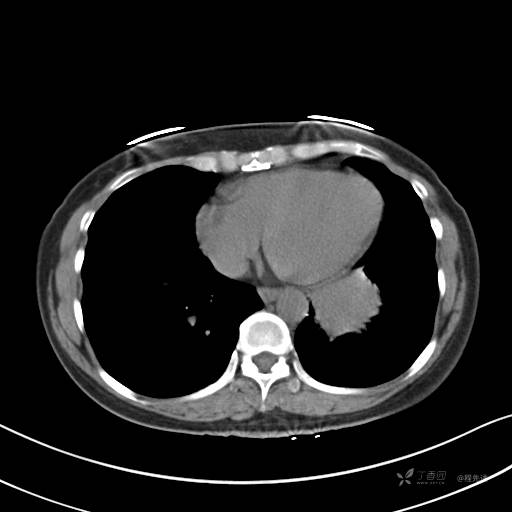

增强动脉期

动脉期CT值约74HU